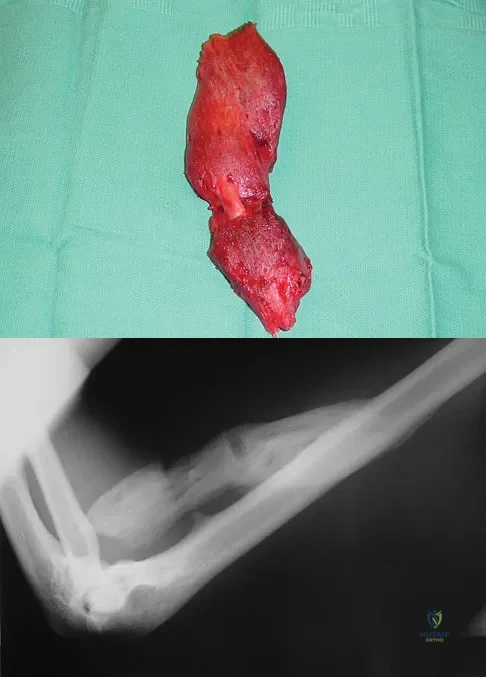

A 47-year-old woman has had left medial clavicle pain for the past 6 months. History is remarkable for mediastinal non-Hodgkin's lymphoma, treated with mantel radiation 22 years ago. A radiograph, CT scan, MRI scan, and a biopsy specimen are shown in Figures 68a through 68d. What is the most likely diagnosis?

Explanation